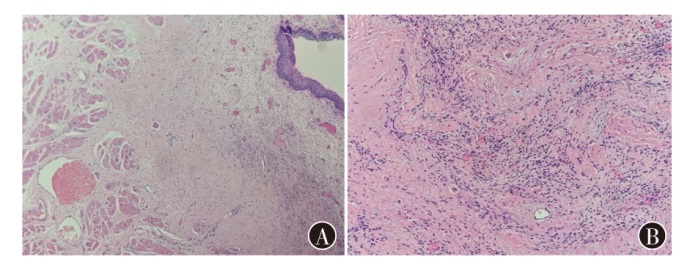

治疗头颈部软组织肉瘤对于完整切除和功能保护有较高的挑战。现报道1例声门上区喉滑膜肉瘤患者的诊疗经过,并就相关文献进行复习,以提高对该类疾病的认识。